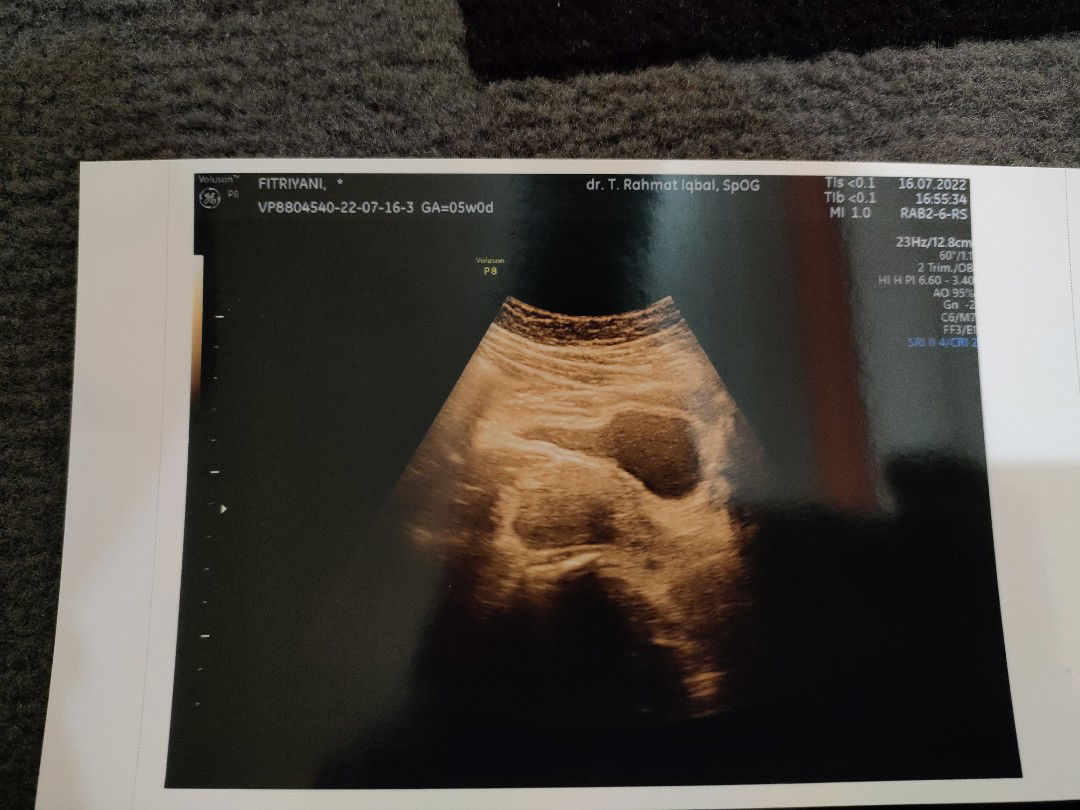

Hamil 6 Minggu 3 hari,boleh minum Paracetamol GK ya? Karna demam dan sakit gigi,info dong Bun🙏

Hamil pertama